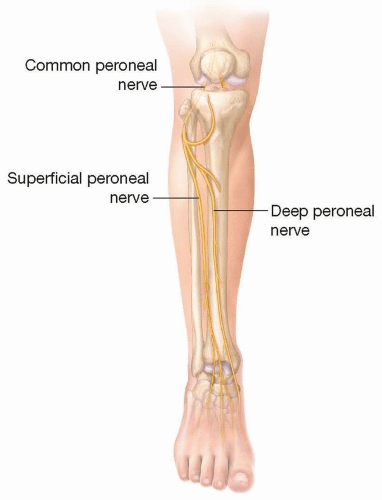

ANATOMY

The common peroneal nerve fibers originate from L4 to S3 nerve roots (FIG 1).

The common peroneal nerve branches from the sciatic nerve in the popliteal fossa.

The motor component of the peroneal nerve innervates the anterior and lateral lower leg compartment muscles as well as some intrinsic muscles of the foot.

The sensory component of the peroneal nerve supplies the first dorsal web space of the foot and the top of the foot.

The peroneal gives off the lateral sural cutaneous branch, which joints the medial sural cutaneous branch (contributed from tibial nerve) to form the sural nerve.

The common peroneal nerve crosses from posterior to anterolateral around the neck of the fibula.

The peroneal nerve is susceptible to compression as it wraps around the fibula.

Once the nerve crosses anterior to the fibula, it branches into the superficial peroneal and deep peroneal nerves.

The superficial peroneal nerve passes straight down the lateral compartment.

The superficial peroneal nerve supplies motor to the lateral compartment (peroneus longus and peroneus brevis).

The superficial peroneal nerve supplies sensation to the top/lateral portion of the foot.

The nerve transitions from within the muscle to a more superficial subcutaneous position at the junction of the middle and distal thirds of the lower leg. This transition site can be a point of compression.

The deep peroneal nerve turns acutely around the fibular neck to enter the anterior compartment of the leg. The deep peroneal nerve then passes under the intermuscular septum between the anterior and lateral compartments to eventually course down between the tibialis anterior and extensor hallucis longus alongside the anterior tibial artery.

The deep peroneal motor nerve supplies the anterior compartment of the leg as well as some of the small foot extensor muscles: tibialis anterior, extensor digitorum longus, peroneus tertius, extensor hallucis longus, extensor digitorum brevis, and extensor hallucis brevis.

The deep peroneal nerve supplies sensation to the first web space of the foot.